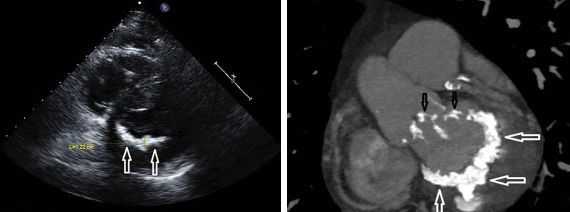

По рентгенограмме при сочетанных пороках сердца нередко визуализируется гипертрофия миокарда, расширение камер сердца, застойные явления в легких и т. д. Наиболее информативным видом диагностики сочетанных пороков сердца служит эхокардиография с допплеркардиографией, дающая четкое представление о состоянии клапанного аппарата, наличии дефектов перегородок, патологической внутрисердечной гемодинамики.

МСКТ или МРТ сердца позволяют рассмотреть послойное пространственное изображение структур органа, что является особенно ценным для диагностики сочетанных пороков. Более точная топическая и дифференциальная диагностика сочетанных пороков сердца осуществляется с помощью специальных методов исследования - вентрикулографии, аортографии, зондирования полостей сердца, флебографии. Пациентам с сочетанными пороками сердца и ИБС требуется проведение коронарографии.

Рентгенография грудной клетки обнаруживает признаки венозного застоя в легких, расширение тени верхней полой вены, преобладающее расширение границ правых отделов сердца. Электрокардиографические признаки трикуспидального порока характеризуются гипертрофией и перегрузкой правого желудочка и предсердия, неполной блокадой правой ножки пучка Гиса, фибрилляцией предсердий. Эхокардиография позволяет выявить морфологическую основу порока (органические поражения трехстворчатого клапана, поток регургитации на трикуспидальном клапане и сопутствующие изменения сердца). Степень гемодинамических изменений уточняется в ходе вентрикулографии и катетеризации полостей сердца.